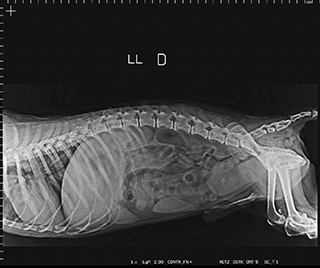

Radiologia Digital Direta / Digital Radiography

As radiografias geradas digitalmente podem ser transmitidas para iPad Apple®, notebooks e smartphones.

iPad com tela Retina Apple® possibilita a visualização das imagens com maior qualidade diagnóstica.

O treinamento aborda a geração das radiografias, a edição digital das imagens, e também a

escolha adequada de técnicas radiográficas como kilovoltagem, corrente elétrica e tempo de exposição.